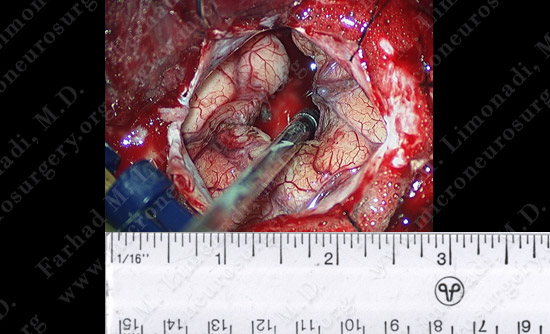

View through the surgical microscope shows the patient’s temporal lobe (brain) is exposed and the tumor is removed while he was awake and his speech was examined during the procedure.